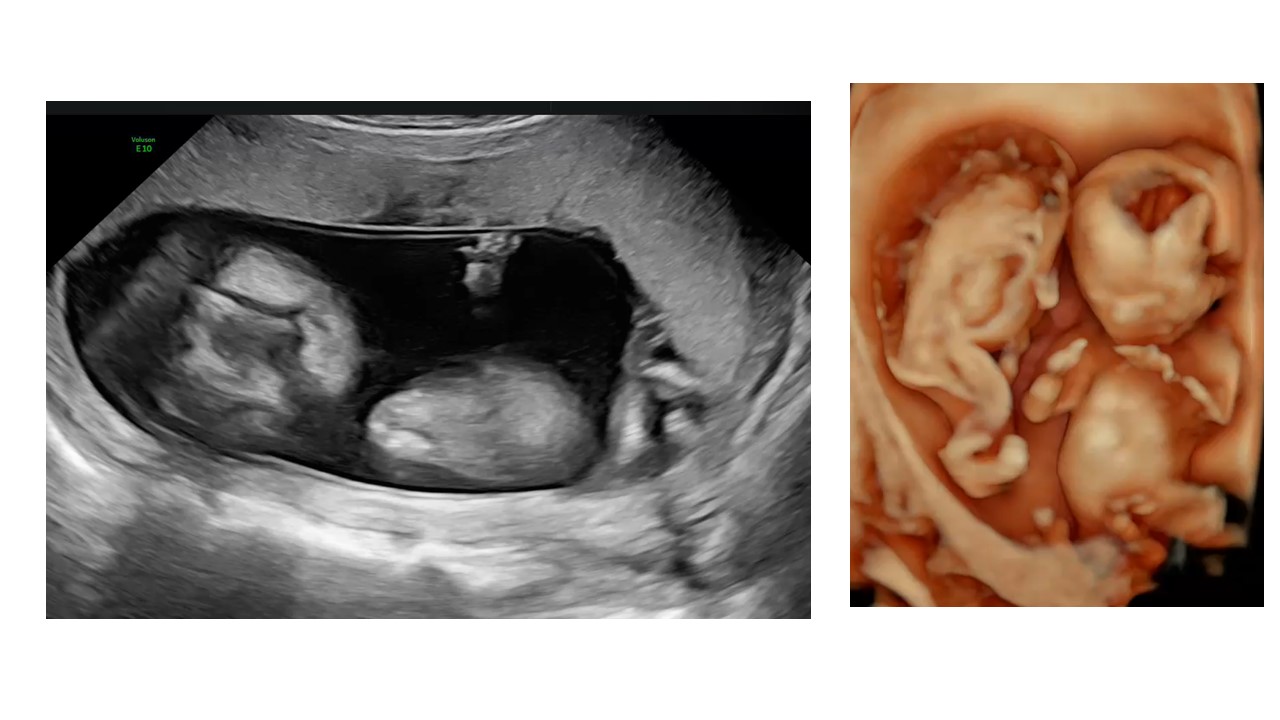

Cập nhật chẩn đoán và xử trí đa thai

BS Hà Tố Nguyên - Trung tâm Y học Bào Thai BV Đa khoa Tâm Anh TPHCM